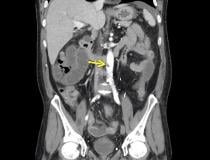

This photo gallery shows the variety of radiological presentations of COVID-19 (SARS-CoV-2) in medical imaging, including computed tomography (CT), radiograph X-rays, ultrasound, echocardiograms and magnetic resonance imaging (MRI). The radiology images show examples of typical COVID pneumonia in the lungs and the numerous complications the virus causes in the body in multiple organs, including the brain, kidneys, heart, abdomen and vascular system.

Ultrasound, especially hand-held ultrasound imaging devices, have become a primary imaging modality for novel coronavirus because of the ease to bag the device and sterilize it after use. CT and mobile X-ray systems are also used as front-line imaging systems for COVID-positive or suspected COVID patients.